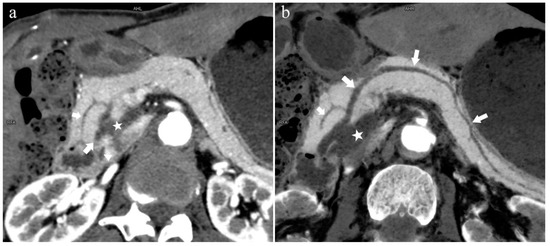

The MPD flowed into the MP, and no APD was the most common anatomical type (type 3b, Figure 4) (58.5%, 473/808); the second type was a classical double division with the double duct structure (type 1, Figure 5) (28.0%, 226/808).

Figure 4.

Type 3b, 63-year-old male patient with AP. (a): MIP [45 keV MEI (+)] shows an S-shaped dilated MPD (long arrow) in the head of the pancreas. APD is not displayed. The fat space around the head of the pancreas is blurred (short arrow). (b): MinIP [45 keV MEI (+)] clearly shows the overall shape of “S”-shaped MPD.

Figure 5.

Type 1. A 68-year-old male patient with IPMN. (a): MIP [45 keV MEI (+)] shows a tumor (pentagram) and the dilated MPD (long arrow) in the head of the pancreas. APD (short arrow) drained from MiP and communicated with MPD. The common bile duct (arrow) is clearly visible. Postoperative pathology confirmed that the mass was IPMN. (b): MinIP [45 keV MEI (+)] clearly shows the overall direction of MPD.